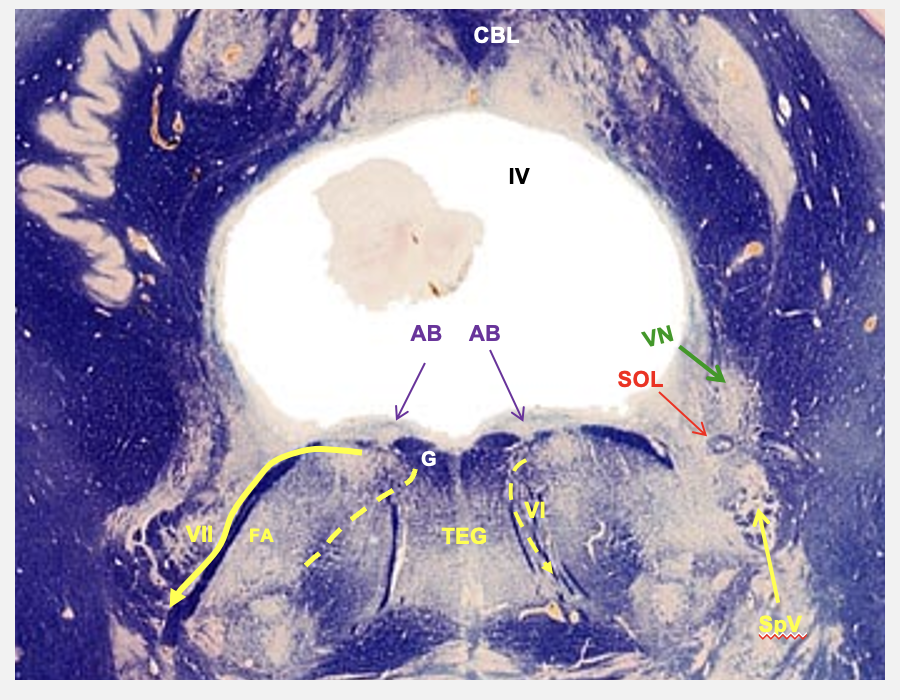

pontomeduallary junction cross section cranial nerve nucelus

caudal pons

abudecens nucleus

cranial nerve 6; somatic motor - neurons here given rise to axons that leave the brain and innervate lateral rectus of the eye

facial nucleus

cranial nerve 7; branchial motor - neurons in this nucleus innervate muscles that control facial movements

dorsally

medially

internal genu

laterally

ventrally

pathway of facial nucleus

axons leave the nucleus and course BLANK and BLANK toward abducens nucleus, on reaching the dorsal surface of pons, they curve around abducens nerves and form the BLANK BLANK, then they go back BLANK and BLANK to exit the lateral side of the brainstem

abducens nucleus

nucleus solitarius

vestibular nucelus

spinal and tract of V

cranial nerve nuceli seen in the cross-section of dorsal caudal pons